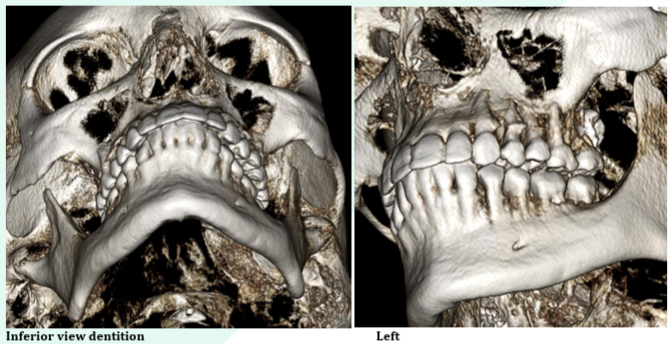

– Precise measurements and high-resolution annotated screenshots

Evaluating for implants

Bone measurements for implant planning

Sinus evaluation

TMJ evaluation

Head and neck reporting

Reporting of CBCT scans done your practice

Find some sample reports in PDF here: